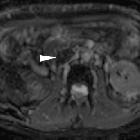

Isolated

intracaval recurrence of resected renal carcinoma. Unenhanced T2- (a-d) and T1-weighted (e) images showed tumour thrombosis in the intrahepatic vena cava (arrows) and normal flow-void signal at the hepatic vein confluence (arrowheads).